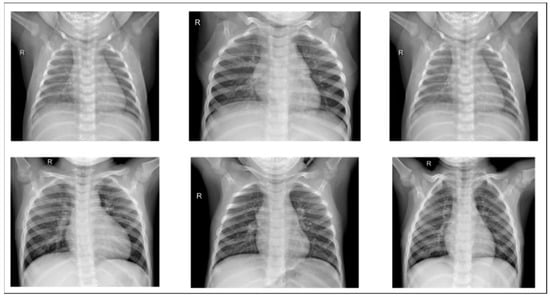

We used an open-source dataset provided by the Kaggle data science competition platform for training (https://www.kaggle.com/paultimothymooney/chest-xray-pneumonia accessed on 25 March 2018) [31]. The dataset comprised thoracic cavity images from child patients (1 to 5 years old) from the Guangzhou Women and Children’s Medical Center, China. These images were classified by two expert physicians and separated into training, test and validation sets. Figure 8 displays the dataset structure, with training sets including 1341 and 3875, test sets 234 and 390, validation set 8, and eight normal and pneumonia images, respectively. Figure 9 and Figure 10 show examples of normal and pneumonia thoracic cavity X-ray images, respectively.

Figure 9. Example normal thoracic cavity X-ray images from the study dataset [31].